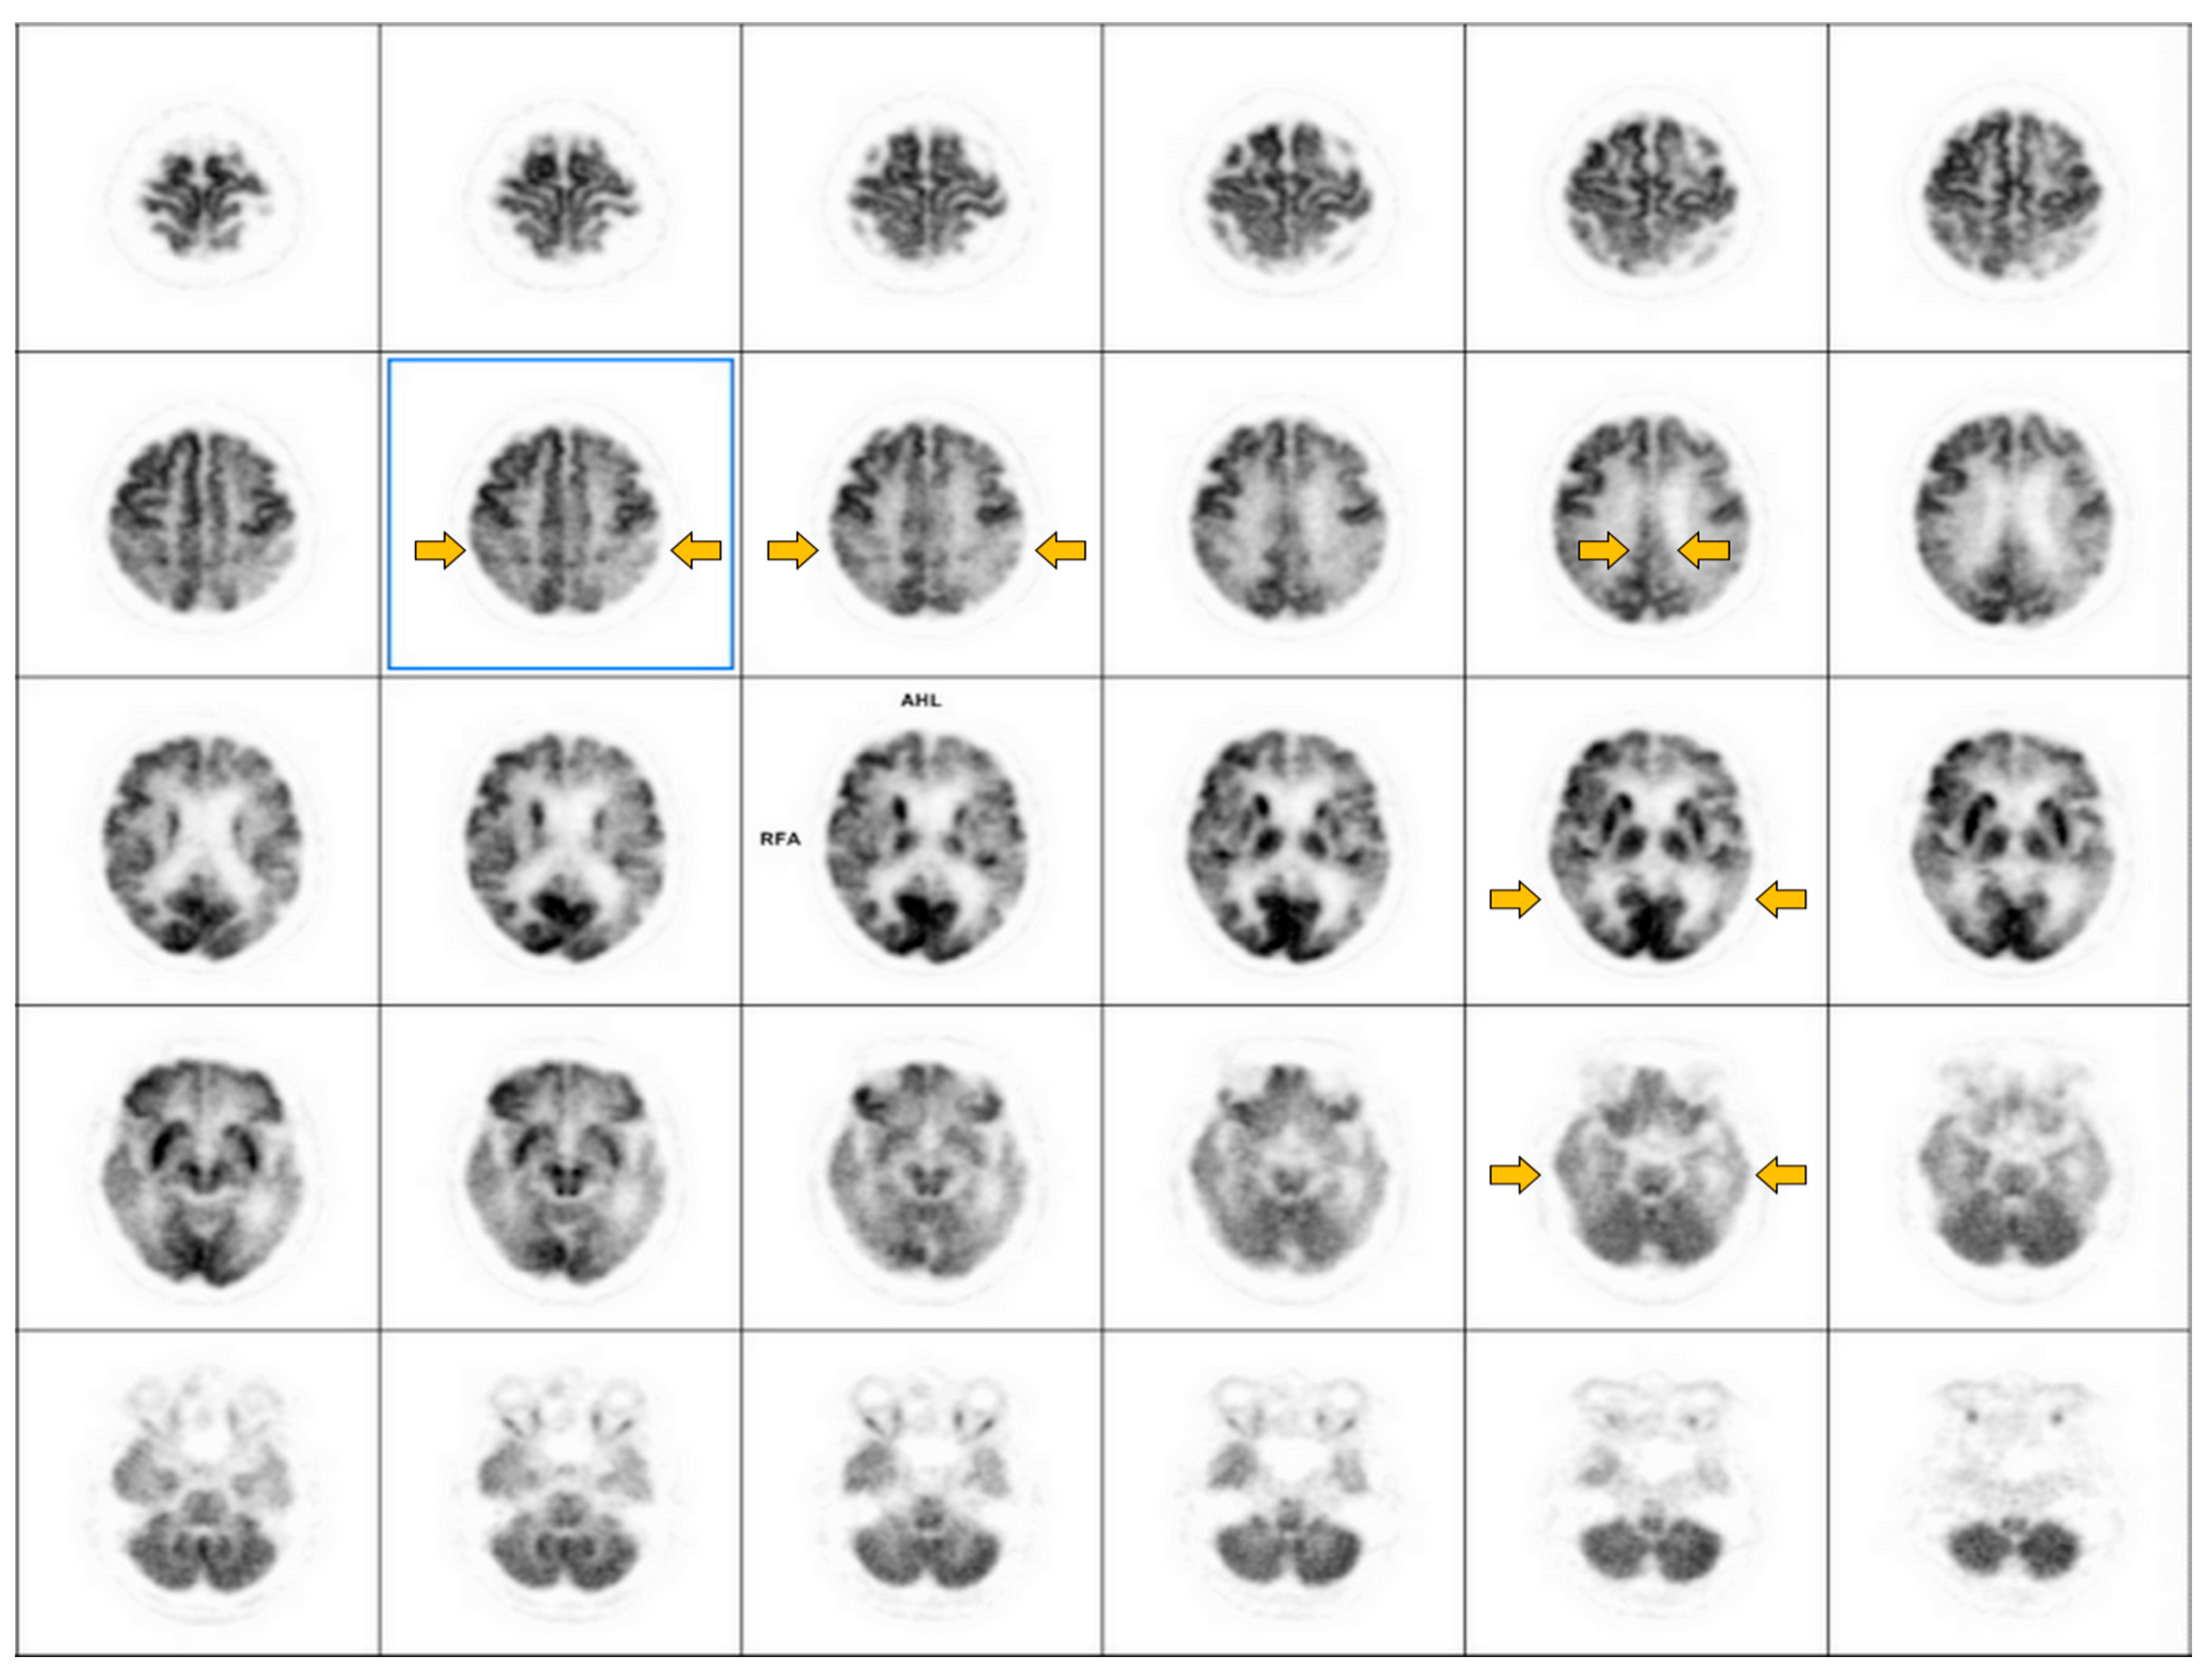

6.1. Brain Perfusion SPECT and FDG PET

6.1.1. Imaging Data Display [45,50]

6.1.2. Image Interpretation for Brain Perfusion SPECT and FDG-PET

| Dementia Type | Hypoperfusion/Metabolic Cortical and Subcortical Regions | Preservation of Perfusion/Metabolism |

|---|---|---|

| Alzheimer’s disease (AD) |

|

| Dementia with Lewy bodies (DLB) |

| Frontotemporal lobar degeneration (FTLD) |

| Vascular dementia |